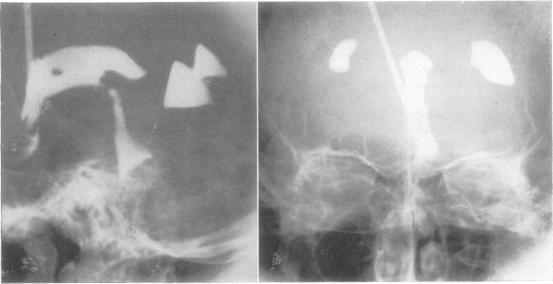

Posterior fossa subdural haematomas.

Traumatic posterior fossa subdural haematomas are rare and, while part of a major head injury, may give little warning of their presence. A definite proportion of cases will be well enough to exhibit progressive and recognizable posterior fossa signs that might include occipital headache, raised intracranial pressure, lateralized cerebellar or brain-stem signs, and a fracture of the occipital bone. These cases will be readily amenable to investigation and cure by evacuation of the causative haematoma.